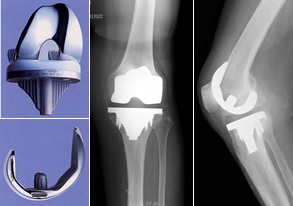

手術では、痛んだ軟骨を金属などの人工材料に置き換える人工膝関節置換術が主流となっています。

https://www.chugokuh.johas.go.jp/kansetsu/knee_joint/operation.html 中国労災病院人工関節センターより引用

他には、変形を矯正する膝関節周囲の骨切り術といったのもあります。